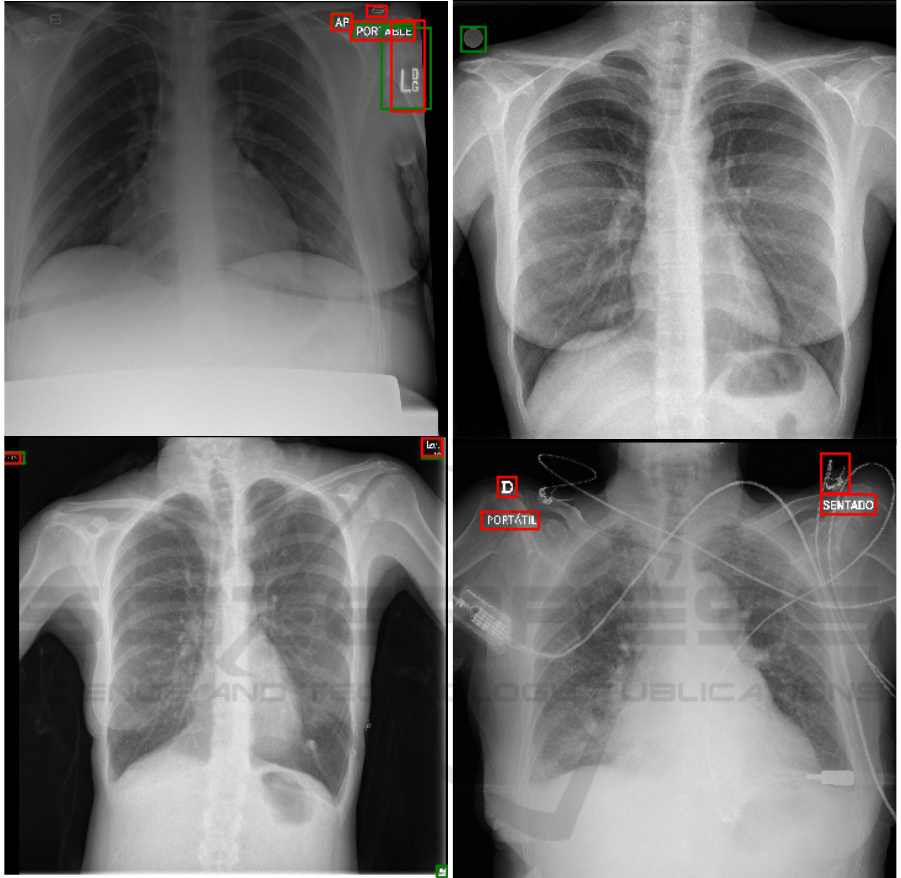

ordinates. Figure 1 shows examples of manually an-

notated bounding boxes.